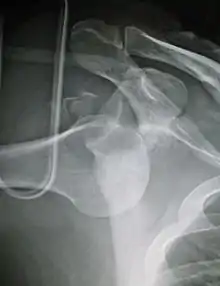

| Anterior dislocation of the left shoulder. | |

In over 95% of shoulder dislocations, the humerus is displaced anteriorly.[7] In most of those, the head of the humerus comes to rest under the coracoid process, referred to as sub-coracoid dislocation. Sub-glenoid, subclavicular, and, very rarely, intrathoracic or retroperitoneal dislocations may also occur.[8]

Anterior dislocations are usually caused by a direct blow to, or fall on, an outstretched arm. The person typically holds his/her arm externally rotated and slightly abducted.

An anterior dislocation of the shoulder

Anterior dislocation of the right shoulder. AP X ray